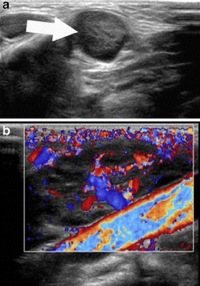

Il risultato dell�ecografia della tumefazione sottomandibolare � riportato nella Figura 1.

Figura 1. Ecografia del collo in sede sottomandibolare sinistra. Presenza a livello del reperto obiettivo di un pacchetto linfonodale con linfoadenomegalie strettamente contigue, con ecostruttura disomogeneamente ipoecogena con diametro compreso entro 28 mm (a), compatibile con iniziale colliquazione, con aumentato flusso ematico al color doppler (b).